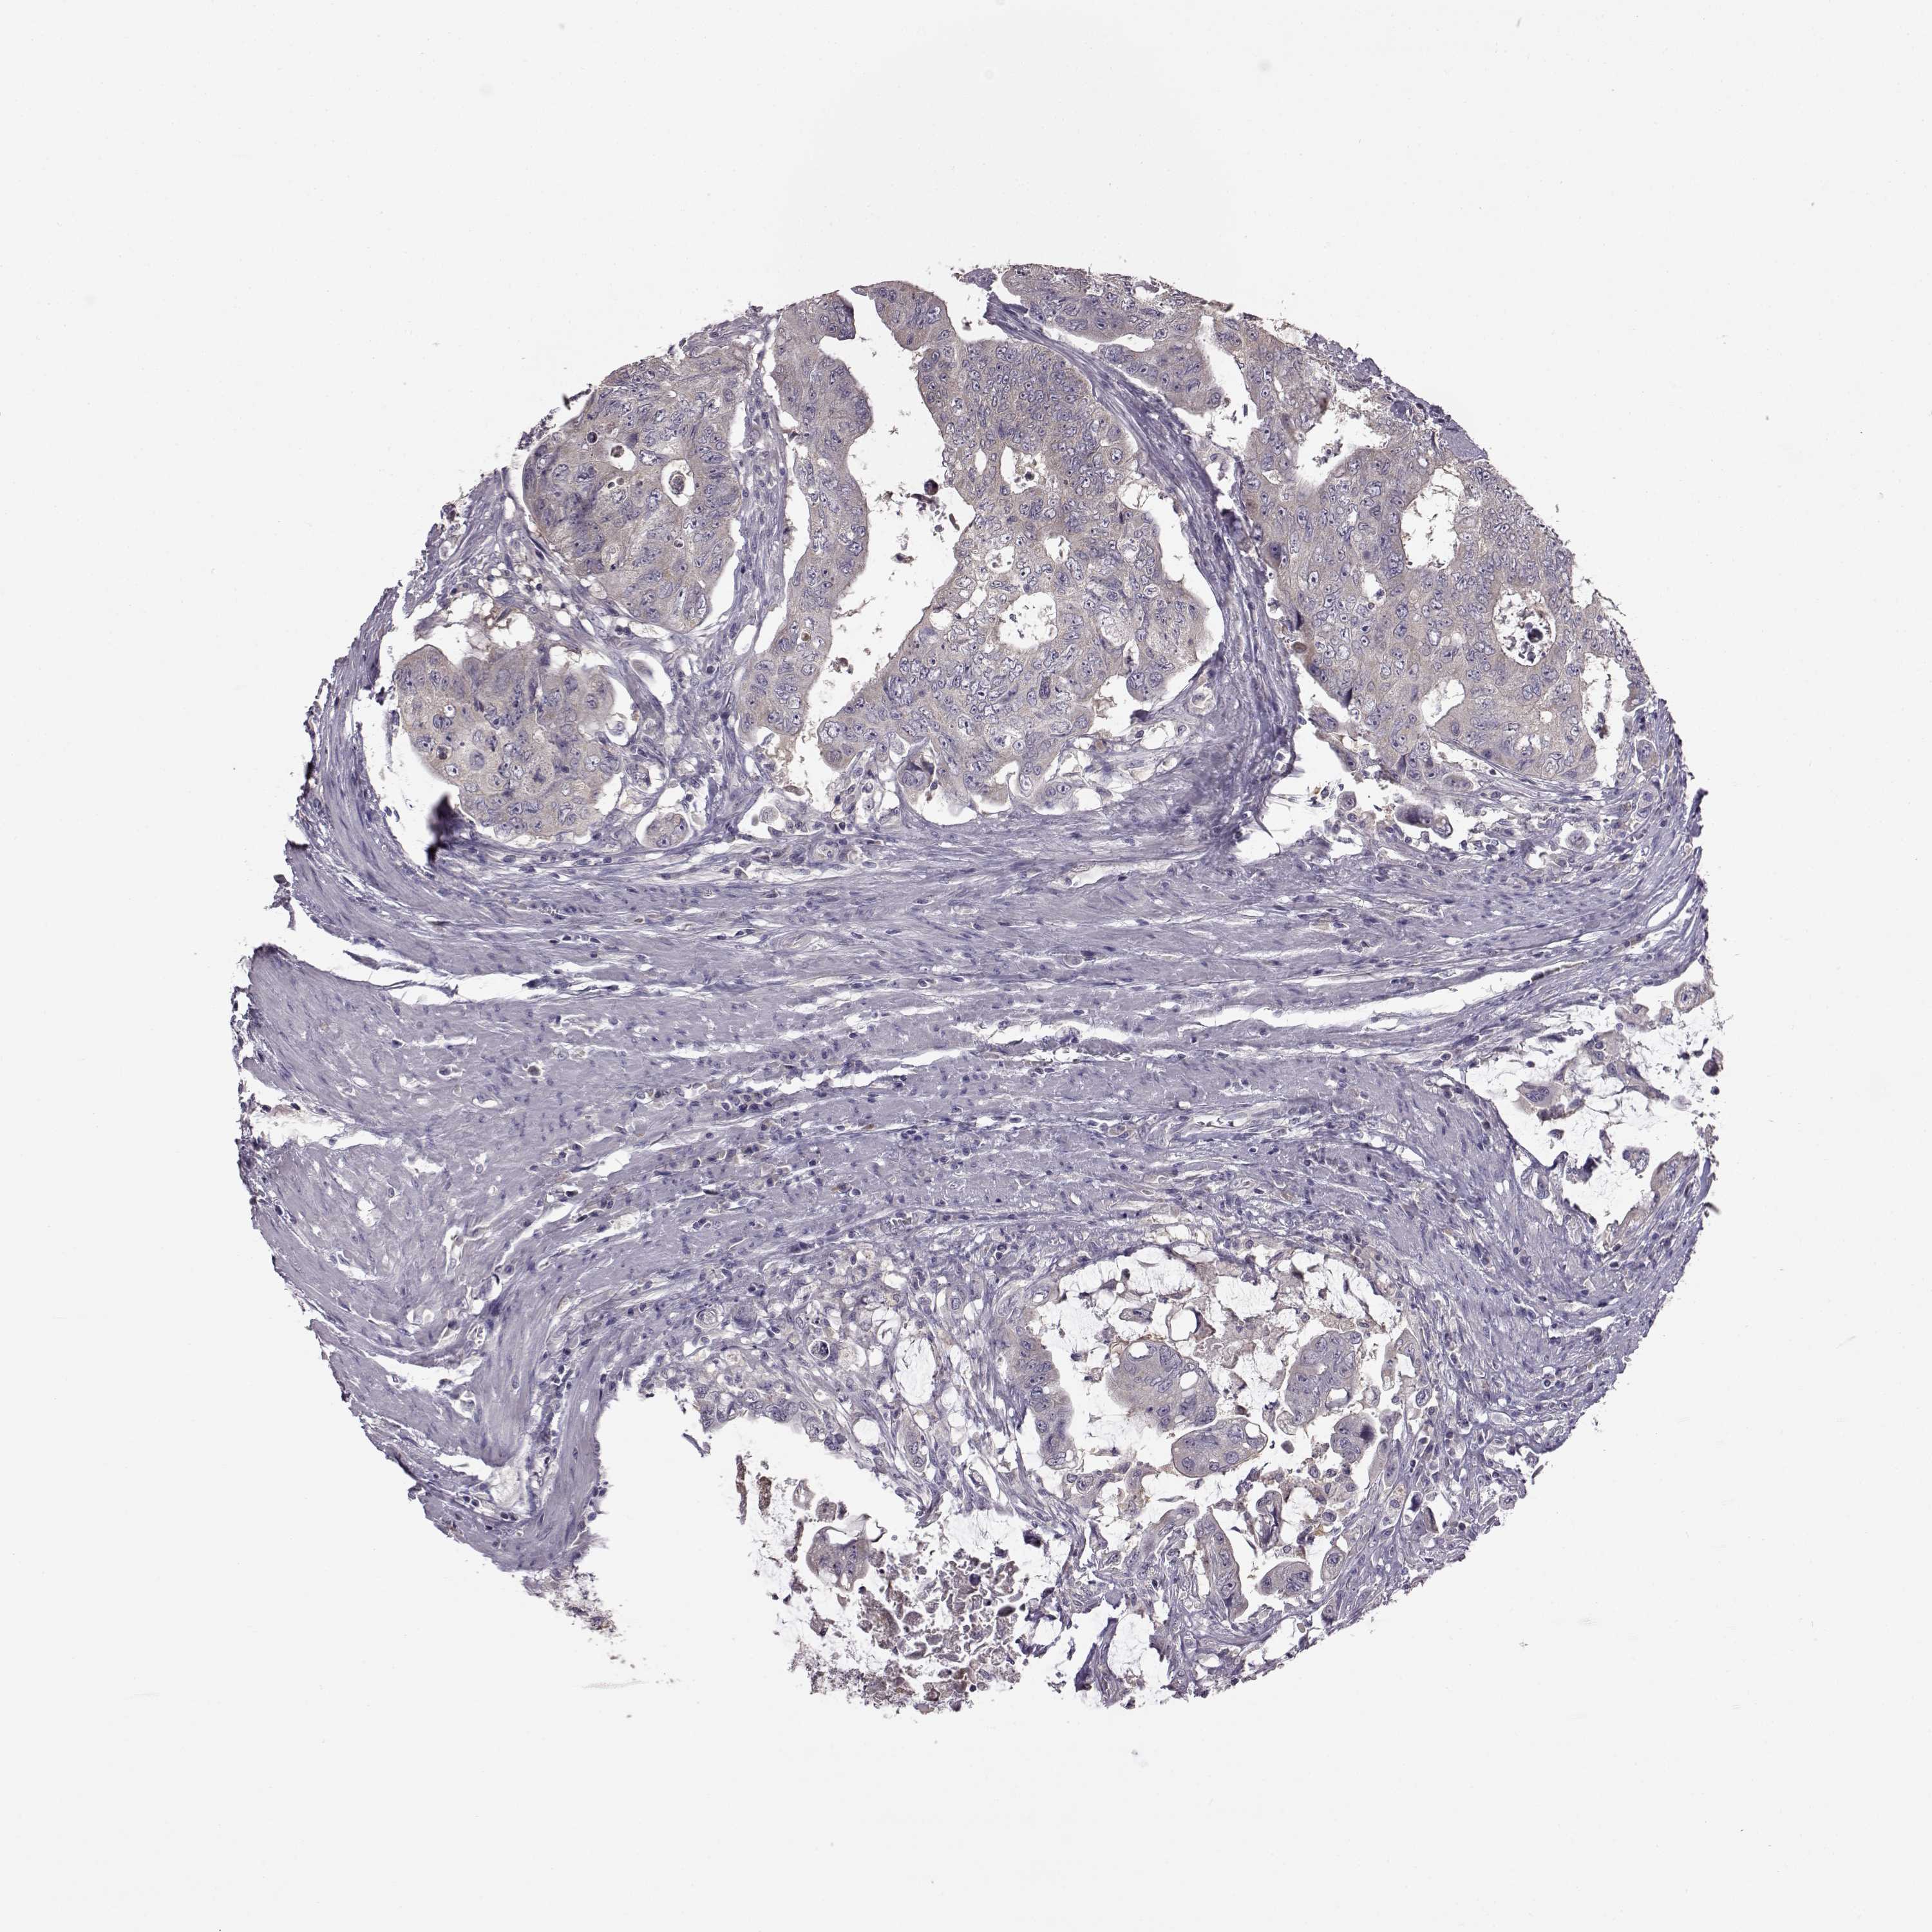

CANCER COLORECTAL CANCER Show tissue menu

Colorectal cancer

Colon adenocarcinoma